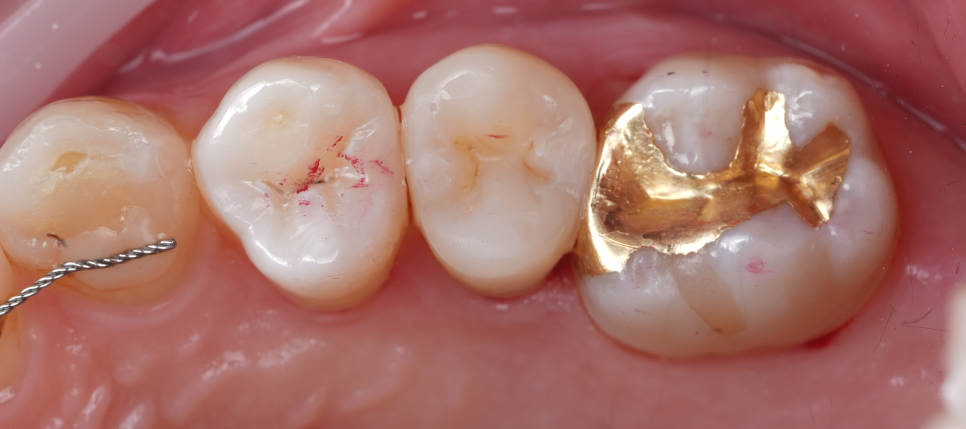

남아 있는 치아는 그대로, 형태만 다시 복구했어요.

바로 치료를 시작했습니다.

촬영일 : 251124

기존에 남아 있던 충전물·임시재를 깨끗이 제거해서 충치와 재료 경계를 깔끔하게 정리했고 안쪽 바닥은 보험이 되는 재료(GI)로 두 면을 먼저 채워 뼈대(바탕)를 만들어 주기로 했죠.

이후 그 위에 신경치료를 위해 만든 구멍을 메우는 작업(코어, Core)와 함께 씹는 면 전체를 포괄적으로 덮는 레진 빌드업으로 형태(교두와 벽)를 다시 만들어 드렸어요.

쉽게 말하면 안쪽은 단단하게 기초를 다지고 바깥은 레진으로 치아 본래 모양과 기능을 다시 만들어 드린 것이라고 생각하시면 됩니다.